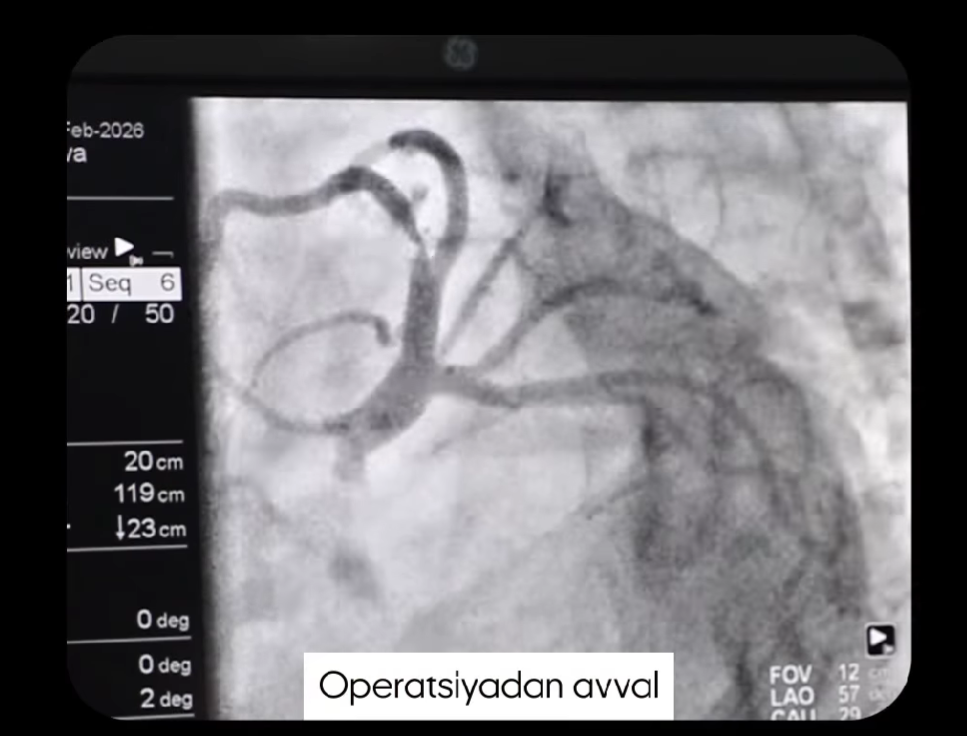

Bu — oddiy jarrohlik emas. Bu jarayon yurak-qon tomir tizimi bilan ishlashni talab qiladigan, juda yuqori aniqlik va katta tajribani talab qiladigan angiografik amaliyot hisoblanadi. Bunday muolajalar maxsus jihozlangan operatsiya xonalarida, zamonaviy angiografiya uskunalari yordamida amalga oshiriladi. Shifokorlar maxsus monitorlar orqali qon tomirlari va yurak tuzilishini real vaqt rejimida kuzatib turishadi.

Angiografik amaliyotlarda eng muhim omillardan biri — aniqlikdir. Chunki jarayon davomida juda ingichka kateterlar qon tomirlari orqali yurak yoki boshqa zarur hududlarga yetkaziladi. Shifokorlar bu kateterlar yordamida muammoning aniq joyini topadi va kerakli davolash muolajasini amalga oshiradi. Shu sababli bunday amaliyotlar katta tajribaga ega mutaxassislar tomonidan bajariladi.

Bundan tashqari, angiografik muolajalar ko‘pincha minimal invaziv usul hisoblanadi. Ya’ni tanada katta kesmalar qilinmaydi, jarayon kichik teshik orqali maxsus asboblar yordamida bajariladi. Bu esa bemor uchun bir qator afzalliklarni beradi: tiklanish davri qisqaroq bo‘ladi, operatsiyadan keyingi og‘riq kamroq kuzatiladi va bemor odatda tezroq kundalik hayotiga qayta oladi.

Shu sababli angiografik amaliyotlar zamonaviy tibbiyotda yurak-qon tomir kasalliklarini davolashda muhim o‘rin egallaydi. Yuqori aniqlik, zamonaviy texnologiya va tajribali shifokorlar birgalikda samarali natijaga erishishga yordam beradi.